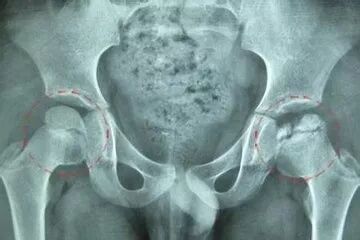

【初期阶段】刚开始是髋关节偶尔各种痛(酸麻胀痛掺杂)、但基本上不影响行走、下蹲等活动,影像检查股骨头形态、髋关节间隙等正常,但股骨头骨密度一般存在低密度影区,符合初期股骨头坏死的特征(事实上临床中漏诊率很高,很多医生诊断不出来)。

【中期阶段】随后不断发展恶化成中期股骨头坏死。这个时候髋关节各种疼痛症状加重,走路开始吃力,如行走远点就乏力、跛行,下蹲开始略微受限,穿袜子、穿裤子、盘腿等开始受限,肌肉也开始有所萎缩。影像检查股骨头形态如轮廓开始轻微变扁、髋关节间隙轻微变窄,股骨头死骨区非常明显。

【晚期阶段】由中期阶段发展而来,股骨头已不堪折腾,各种痛不分昼夜、不管是坐着还是躺着还是站着还是走着,疼痛都会如影随形。活动日益受限,穿袜子穿鞋穿裤子下蹲盘腿等一般都明显或严重受限了,当然不能盘腿了,双腿外展明显受限,走路依靠拐杖、上下楼梯吃力而艰难,大部分的患者其病肢的肌肉萎缩明显,影像检查股骨头形态改变明显,如股骨头明显变扁、塌陷,髋关节间隙明显变窄,股骨头骨结构破坏严重,如囊性病变区很多、股骨头塌陷、毛糙化、髋关节半脱位、下肢缩短等等。

【致残期】由晚期股骨头坏死发展而来。股骨头患肢活动基本丧失、患肢肌肉萎缩严重,影像检查显示髋关节间隙基本消失,股骨颈严重萎缩变短,股骨头严重变扁、塌陷,髋关节韧带钙化严重,与瘫痪仅有一线之遥。